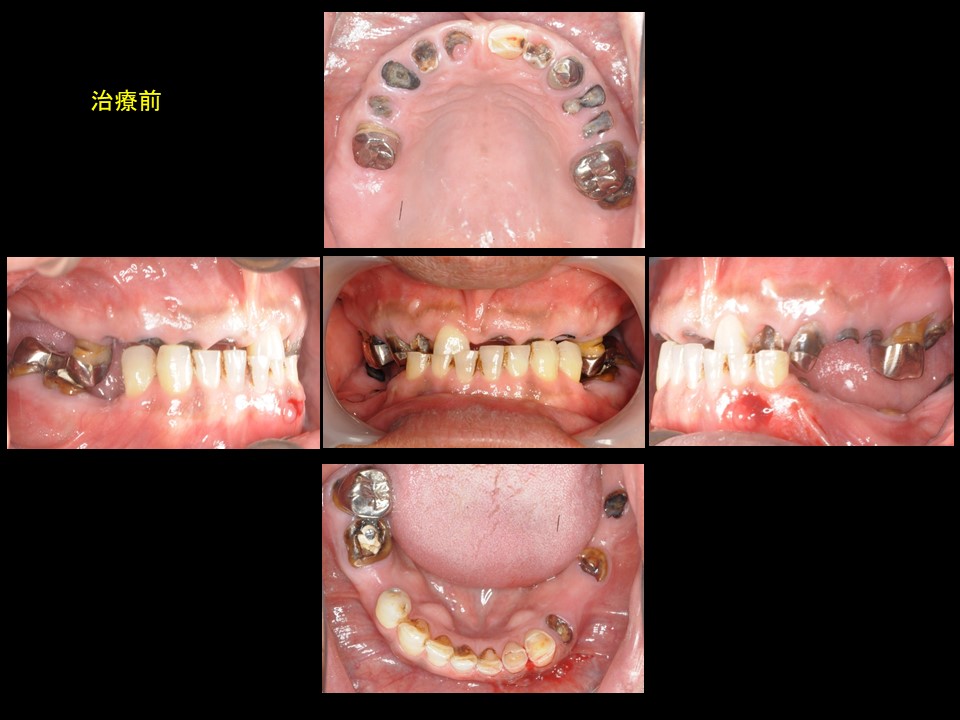

症例6